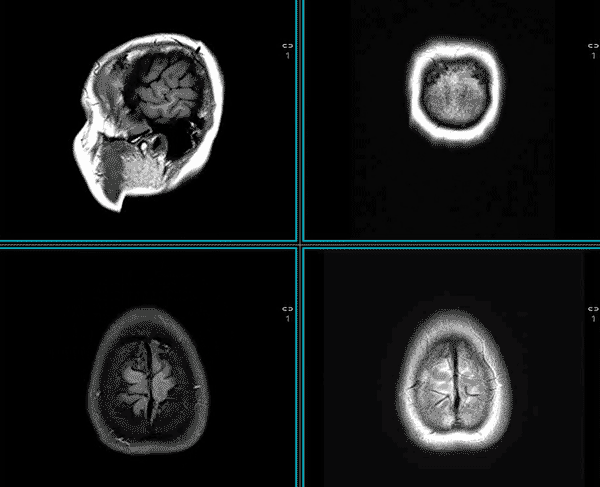

Neuroimaging is a specialized branch of medical imaging dedicated to the diagnosis of neurological disease and the longitudinal assessment of brain health. The acquisition and interpretation of these studies are performed by neuroradiologists, specialists trained in the complex anatomy and pathology of the central nervous system.

Structural imaging of the brain focuses on the anatomical integrity of the brain. It is the primary modality for identifying macro-scale intracranial pathology, including primary and secondary malignancies (tumors), acute cerebrovascular accidents (CVA) and traumatic brain injuries (TBI).

MRI is widely recognised as the gold standard for most musculoskeletal (MSK) and soft-tissue evaluations. This diagnostic superiority is particularly evident in neurology where MRI significantly outperforms CT in identifying the complex underlying etiologies of chronic headache and occult soft-tissue pathology